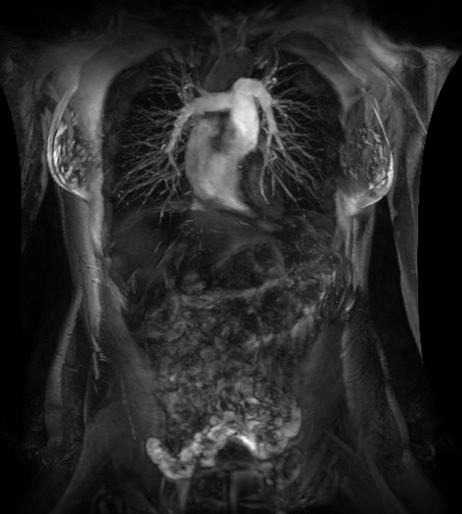

MR,早期肝臟健康(Resoundant)檢查

全面、定量、無輻射、快速(屏氣)和無創(chuàng)的肝臟評估。

定量評估甘油三酯脂肪濃度和R2 *(IDEAL IQ),肝臟組織硬度即時分析(MR Touch)??赡苡兄谠u估非酒精性脂肪性肝病(脂肪)、脂肪性肝炎(炎癥)和肝硬化(纖維化)。致力于讓磁共振成像和活檢一樣精準(zhǔn)、有效。(待FDA 510K審批,未上市銷售)

在乳腺MR檢查中,SIGNAWorks?通過可調(diào)節(jié)線圈元件使得乳腺成像實現(xiàn)定量化和個性化,從而實現(xiàn)精準(zhǔn)醫(yī)療。創(chuàng)新型應(yīng)用——用于超快速動態(tài)掃描的DISCO,用于高分辨率形態(tài)成像的Cube T2 with HyperSense和Cube T2 HyperCube,縮短了掃描時間并促進了擴散技術(shù)(Focus和MUSE)的發(fā)展,利用與BIRADs一致的CADStream來探測組織特征和分析。